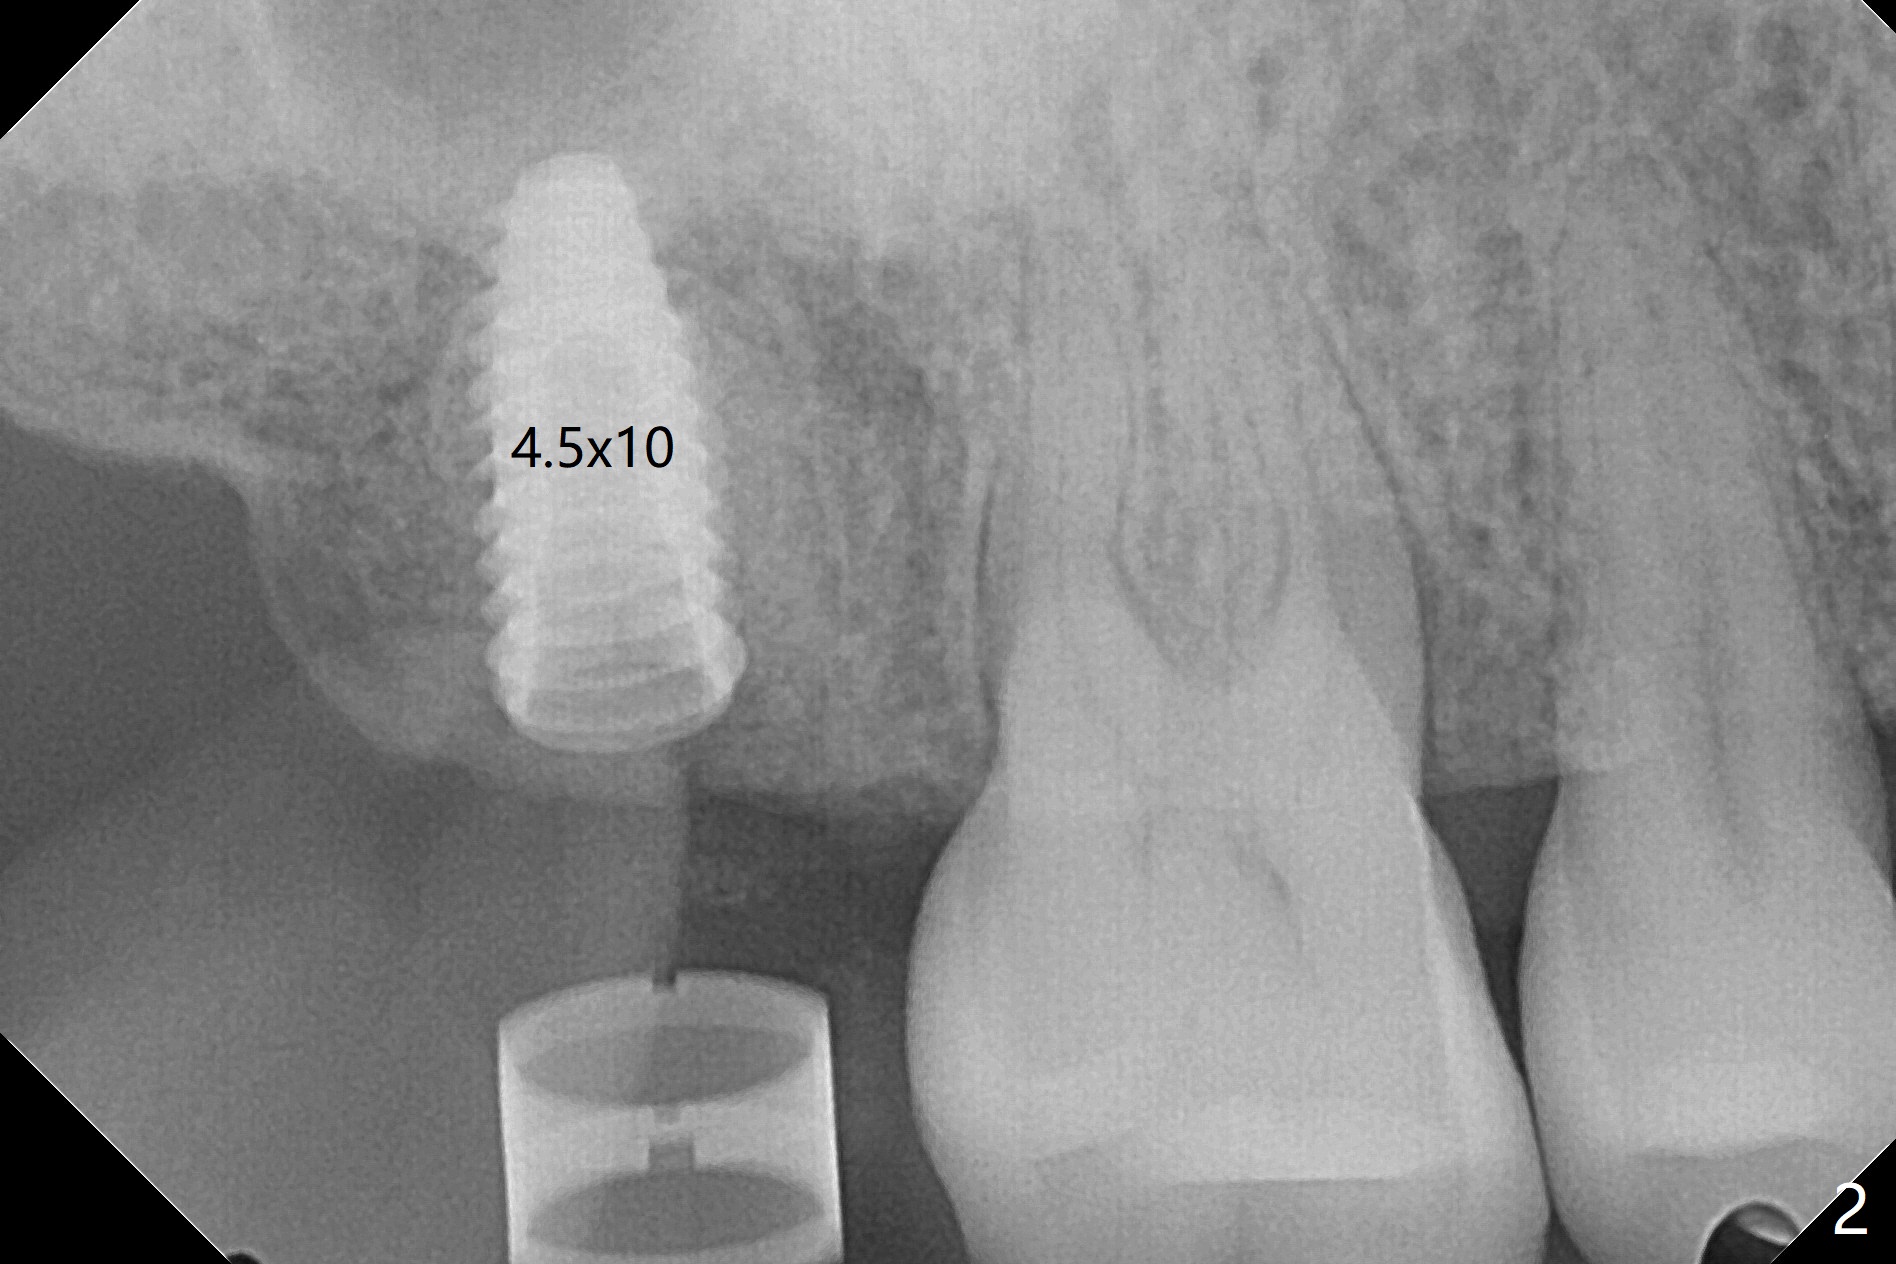

术前CT显示右上7牙槽骨不平,可能造成植体偏移,腭侧,远中螺纹暴露,为了方便导板种植后植骨,切开翻瓣,牙槽骨外形与CT检查一致,不过1.5毫米offset牙槽嵴磨平钻头所形成钻洞正常,除了骨质密度高之外,术中临床和射线检查发现植体方向和种植水平与设计一致,没有偏移(图一至三),最后只有腭侧一个螺纹暴露,放置愈合基台后,放入粘性骨粉,覆盖PRF膜,近中,远中各缝合一针,其余使用牙周胶水关闭伤口。不偏位可能原因:使用1.5毫米offset,骨质密度高,两侧密度接近。术后一周远中伤口裂开(图四:*),近中,远中应该多缝合一针。术后三周伤口愈合。The implant threads are subcrestal 5 months postop (Fig.5).